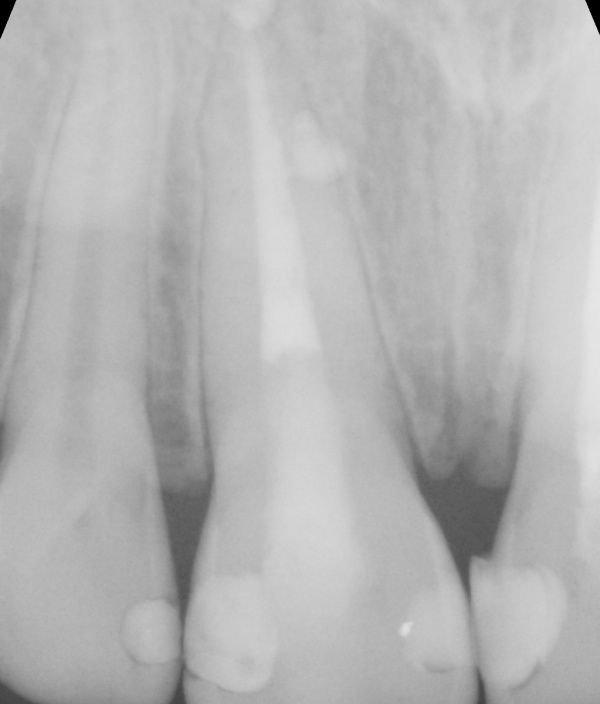

Kalcium silikátové materiály si od svého uvedení na trh získaly pověst vhodných materiálů pro zaplnění širokých kořenových kanálků nebo jiných situací v rámci endodontického ošetření, kde je materiál v kontaktu s nadměrnou vlhkostí.

Zároveň si však získaly pověst materiálů s obtížnou manipulací, což vedlo výrobce k vývoji předmíchaných kalcium silikátových sealerů. Tyto sealery nabízejí jednoduchou manipulaci, zejména při technice hydraulické kondenzace, kdy se zavádí pouze hlavní gutaperčový čep.

V určitých případech může být výhodná pístová technika. V rámci přednášky se dozvíte základní informace o kalcium silikátových materiálech – kdy je vhodné je využít, o kalcium silikátových sealerech – jaké existují, a také praktické informace o pístové technice – jak a kdy ji provést, jak si zjednodušit život a jak se vyhnout komplikacím.